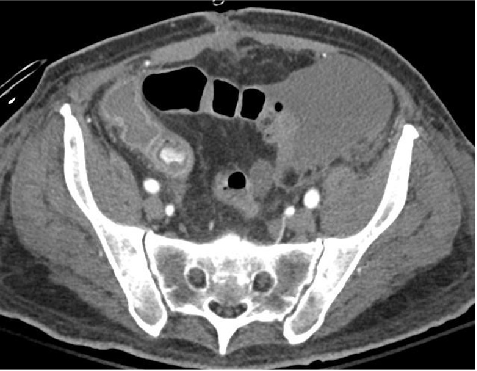

这是一种典型的阶梯式或分流式临床决策逻辑。结合我们之前讨论的所有内容(内镜、CT血管成像、血管造影),我将其解读并扩展如下: 1. 微量出血 (Minor bleeding) —— 保守治疗定义:通常指粪便潜血阳性,或偶尔有少量便血/黑便,但血流动力学稳定,无贫血或仅有轻度贫血。处理:Conservative(保守治疗) 这通常包括观察、饮食调整、使用止血药物(如需要)、以及针对病因的药物治疗(如痔疮栓剂、治疗便秘等)。 此类情况通常不需要紧急住院或急诊内镜干预。 2. 慢性低度出血 (Chronic low-grade bleeding) —— 内镜定义:指长期、间歇性的肉眼血便或持续潜血阳性,通常伴有慢性缺铁性贫血,但无急性血流动力学紊乱。处理:Endoscopy(内镜) o结肠镜是首选,用于排查肿瘤、息肉、炎症性肠病、血管发育不良等慢性出血病因。 o胃镜用于排查上消化道来源(如溃疡、胃糜烂、肿瘤)。 o这类检查通常是择期进行的,可以在充分的肠道准备和优化患者条件后进行,以获得最佳的诊断率和治疗机会(如息肉切除)。 3. 严重出血 — 稳定患者 —— CT定义:患者存在明显的活动性出血(如大量便血或呕血),但血流动力学稳定(血压、心率维持在正常范围,无休克表现)。处理:CT(即CT血管成像,CTA) o目的:快速定位出血点。 o逻辑:对于严重但稳定的患者,急诊结肠镜往往因为视野不清或肠道准备不充分而难以进行。CT血管成像可以快速完成(数分钟),能清晰显示造影剂外溢的位置(阳性结果),为后续的靶向治疗(定向血管栓塞或定向内镜)提供精确的解剖学定位。 o结果解读: §Positive CT – Active Bleeding:如果CT显示活动性出血,则可直接送入介入室进行血管造影+栓塞,或引导内镜精准止血。 4. 严重出血 — 不稳定患者 —— 血管造影定义:患者存在大量活动性出血,且伴有血流动力学不稳定(低血压、心动过速、休克、需要大量输血)。处理:Angiography(血管造影)

o操作:血管造影可以直接显示出血血管并进行超选择性栓塞,迅速阻断血流,达到止血目的。这是稳定危重患者生命体征的最快介入手段。o逻辑:这类患者无法耐受耗时的肠道准备(结肠镜),也无法安全地转运至CT室进行扫描(或者在CT室发生意外风险高)。通常由急诊直接送入介入放射科或杂交手术室。 总结:决策流程图结合你提供的这四点,可以构建出以下清晰的决策树:![]() 关键补充1. CT血管成像的桥梁作用:你提到的“Severe bleeding stable patients > CT”在现代急诊处理中非常关键。它弥补了结肠镜在急诊状态下的局限性(视野差、准备慢),成为了连接急诊室与介入/手术室的高效桥梁。2. 不稳定患者的直接介入:对于“Severe bleeding unstable patients”,血管造影跳过了CT和内镜,直接进入治疗环节,体现了“Damage Control”(损伤控制)的原则——先止血,再明确病因。 3. 内镜的定位:内镜(结肠镜)主要服务于慢性低度出血(择期精准治疗)和部分严重但视野清晰的病例,但它不再是所有严重出血的“必经之路”。 这种分层策略可以最大限度地保证患者安全(避免不稳定患者进行风险较高的内镜检查),同时提高诊断效率(利用CT快速定位)。如果你需要,我可以将这个策略与你之前整理的“急诊结肠镜表格数据”结合起来,形成一个更完整的临床参考。 Optical Colonoscopy赞成 PROS:

✔ DSA之前 增强CT(Multiphase MDCT without oral contrast always before DSA)